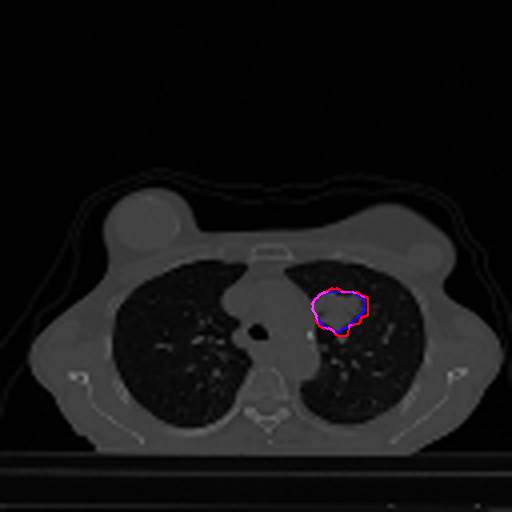

A qualitative analysis of our results reveals the strengths and weaknesses of our proposed model. In most cases, regardless of the size of the ground truth, our model predicts the tumor shapes very well. This is evident from Figure 4 where the ground truth and the prediction (by Deeply Supervised MultiResUNet) are shown in red and blue respectively. Although the tumors are in various arbitrary locations within the lung and appear in diverse sizes, the red and blue margins appear to coincide almost perfectly.

Figure 5 shows a comparison between predictions by the MultiResUNet model and Deeply supervised MultiResUNet model. It can be seen that the latter can delineate the tumor edges more accurately than the former. The ground truth (shown in red) and the prediction (shown in blue) have a more consistent alignment with each other in Deeply Supervised MultiResUNet’s prediction.